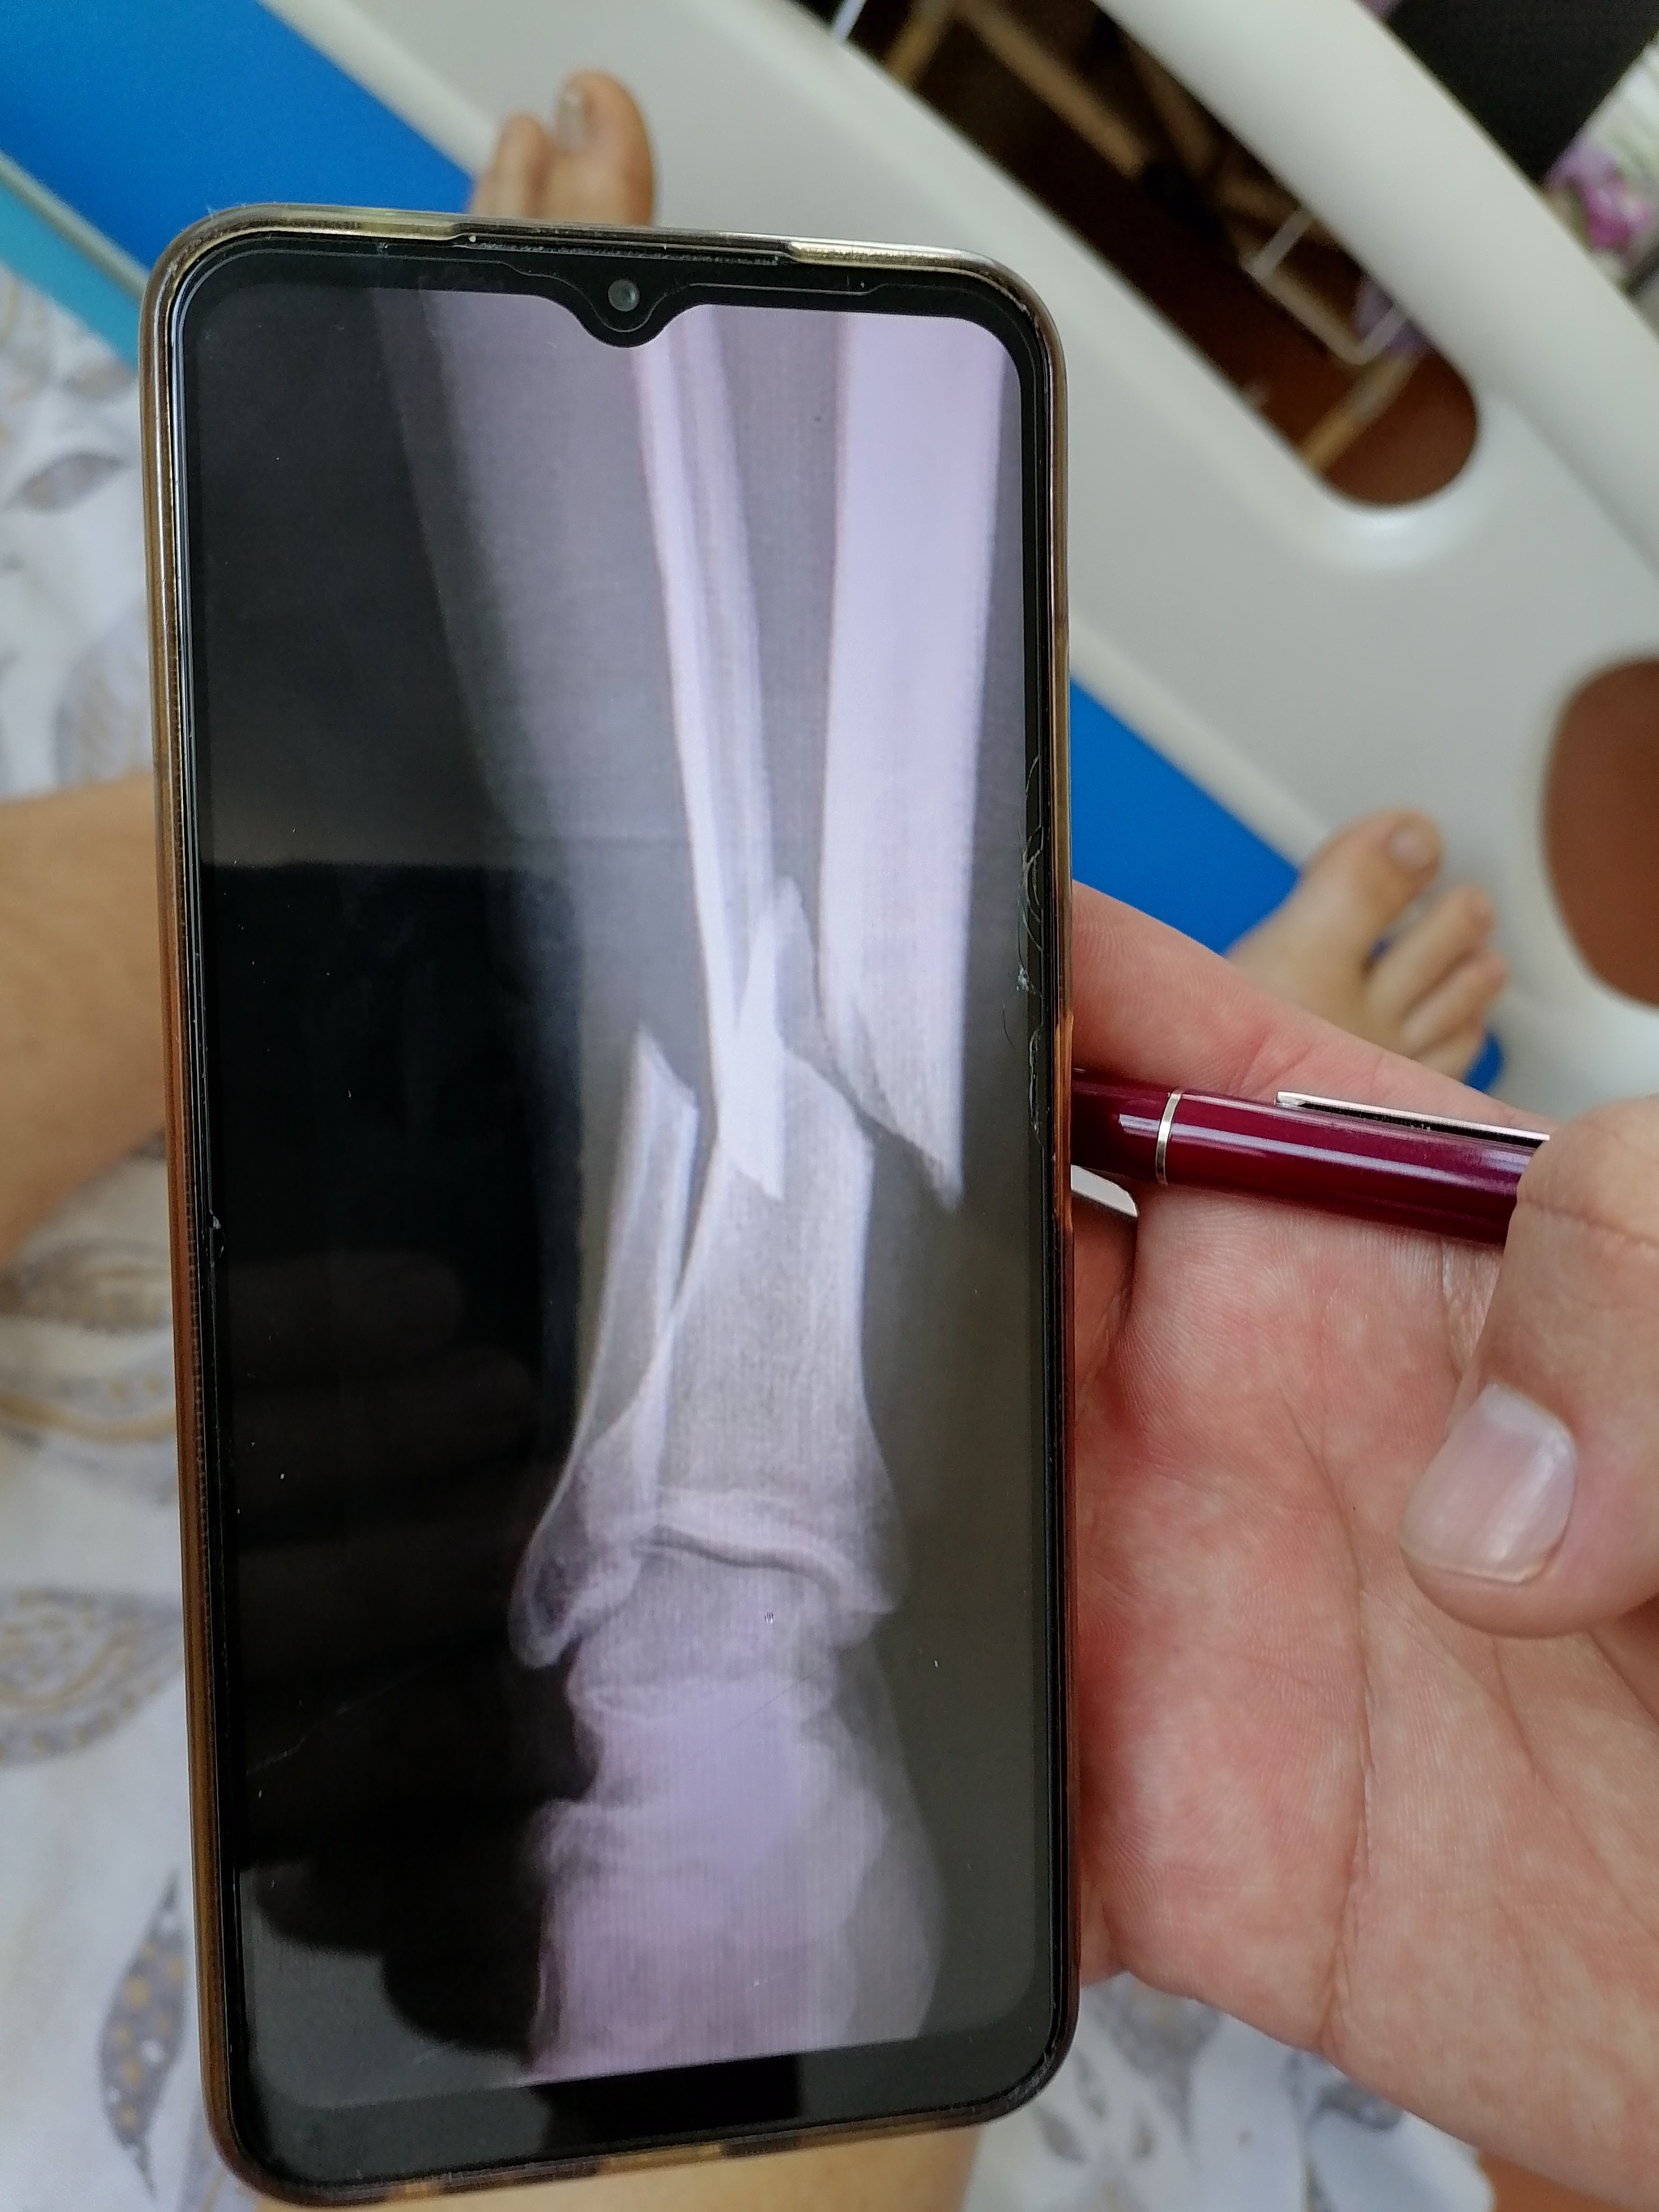

Когда дорога до больницы и очередь в травмпункте были позади я оказался в кабинете у врача который осмотрев визуально моё плечо сказал что это мало вероятно что это ключица и отправил на рентген в соседнем кабинете. Вернувшись к врачу в кабинет я увидел что он уже рассматривает мой снимок на своём компьютере. Врач сказал что хорошо постарался и потребуется операция по установке пластины и начал готовить документы для госпитализации и что бы я не скучал медсестра сводила в процедурный кабинет где поставила укол обезболивающего(до этого я пил только анальгин который не особо помогал при такой боле).

Результат покатушки: Перелом верхнего конца плечевой кости закрытый.